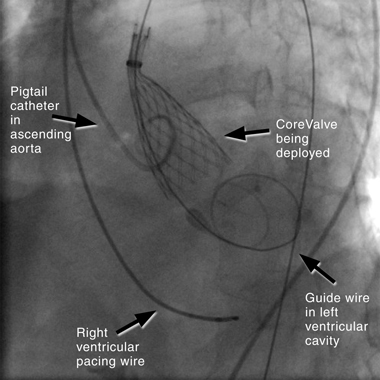

The retrograde approach has undergone rapid modification in recent years, due to the development of specialised closure devices that have allowed for a percutaneous procedure without the need for formal femoral surgical repair.16 It is now by far the most common approach to PAVR, because it is a simpler technique and has procedural similarities to coronary angiography. The technique (illustrated in Box 4) involves inserting a large sheath (18–22F) into the femoral artery, with a pre-closure device. If the subclavian route is used, a surgical cutdown is required, with direct suture closure of the vessel at the completion of the procedure. A right ventricular pacing wire is placed for rapid pacing (220 beats/min) that is performed during BAV and for temporary cardiac pacing if bradycardia occurs. The aortic valve is crossed using a guide wire, and the device is positioned across the valve. The CoreValve is self-deployed, and the Edwards SAPIEN valve is balloon-deployed under rapid ventricular pacing to reduce left ventricular stroke volume and reduce risk of device migration. The large femoral sheath is removed using the pre-closure device.